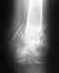

Здравствуйте. Мне 41 год. г. Тобольск. 2 августа получила травму руки: вывих локтевого сустава, перелом головки лучевой кости. рука правая. 29 августа сняли гипс. Контрактура. Начала разработку.

Сделали "магниты" (7 раз). На ЛФК хожу два дня. Упражнения и "ручное" сгибание сустава. Больно. С трудом вериться, что восстановлюсь. Вопрос к специалистам: скажите пожалуйста, из приложенной мной рентгенограммы можно надеяться на выздоровление без повторной операции (удаления части головки)? Какое бы вы посоветовали восстановительное лечение. Сколько оно может занять времени. Извините за терминологию - не специалист.